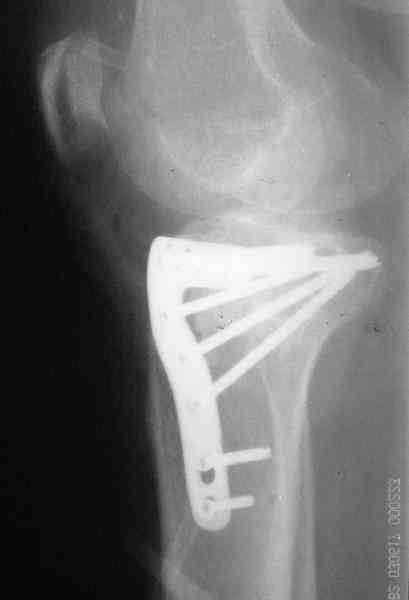

[Ortho] Застарелый перелом 41С3

Уважаемый Абдурашид. Если нет противопоказаний , то из оперативных

способов, я бы рекомендовал следующие: Полное замещение наружного

мыщелка аллотрансплантатом либо открытая репозиция с элевацией и

замещение дефекта ауто или аллокостью. В Ваших условиях , я бы

рекомендовал второй способ. Во-время элевации необходимо разъединить

фрагменты со стороны сустава ( надсечь скальпелем по линиям перелома,

а затем тонким остеотомом их разъединить. При помощи долота произвести

неполную остеотомию ( захватите не менее 1,5 - 2 см губчатой кости и

поднять фрагменты, визуально отрепонировать и фиксировать 2-3 спицами.

Дефект заместить костным ауто или аллотрансплантатом. Окончательная

стабилизация пластиной ( лучше с угловой стабильностью, либо АВФ -

позволит спокойно устранить угловую деформацию.

Недавно поступила больная через 1,5- 2 месяца.